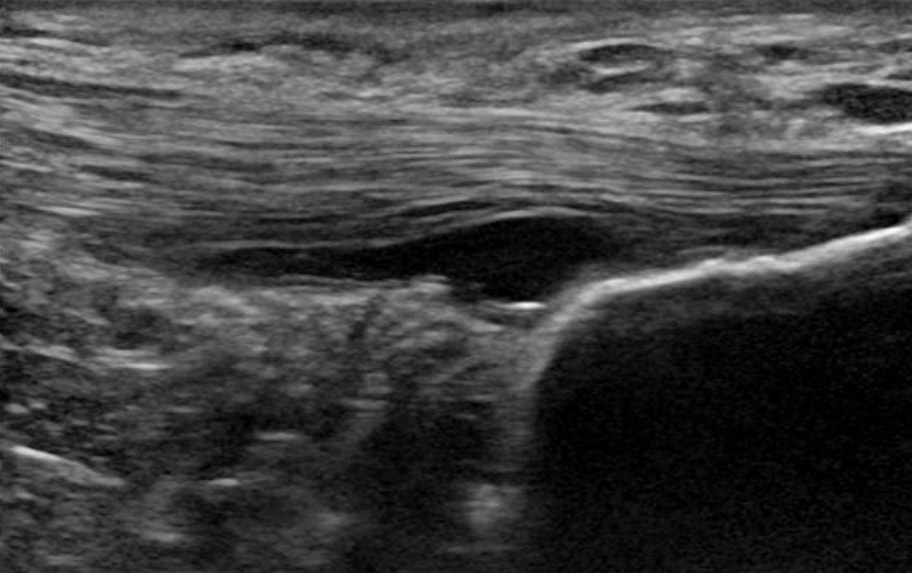

2. Emme pysty korjaamaan/parantamaan degeneratiivista jänteen patologiaa. Toisin sanoen, mikään leikkaus, shokkihoito, injektiot tai edes liikunta eivät pysty korjaamaan tai parantamaan rappeutunutta jännetuppia. Docking et al. (2019) päättelevät, että koska jänteen degeneratiivisen osan solut eivät kykene havaitsemaan vetokuormitusta, ne saattavat olla alistimuloituja eivätkä saa tarvittavia mekaanisia ärsykkeitä uudelleenmuodostukseen, mikä selittää patologisen jänteen rajallisen kyvyn uudelleenmuodostukseen ja normalisoitumiseen. Vaikka luuletkin, että tämä on huono uutinen, hyvä uutinen on, että se ei myöskään ole välttämätöntä. Tsehaie et al. (2017) osoittivat, että 24 viikon eksentriset harjoitteet akillesjänteelle eivät tuottaneet muutoksia jänteessä havaittavan muutoksen rajojen ulkopuolella, mutta silti potilaat paranivat. He havaitsivat myös, että o MRI-parametri lähtötilanteessa ennusti oireiden muutosta, joten vaikka MRI-kuvaus näyttäisi kauhealta, sillä ei ole väliä.

6. Patologisessa jänteessä on enemmän hyvää rakennetta kuin normaalissa jänteessä(Docking et al. 2015). Tämä tarkoittaa, että voimme kuormittaa näitä jänteitä, koska meillä on paljon hyvää kudosta. Jänteen patologian hoitoja ei tarvita, koska emme voi muuttaa patologisen osan rakennetta. Tästä syystä Docking ja kollegansa keksivät sanonnan "Treat the donut, not the hole" - toisin sanoen, keskity terveeseen rakenteeseen, älä patologiseen osaan.

Patologisessa jänteessä on enemmän hyvää rakennetta kuin normaalissa jänteessä (Docking et al. 2015)